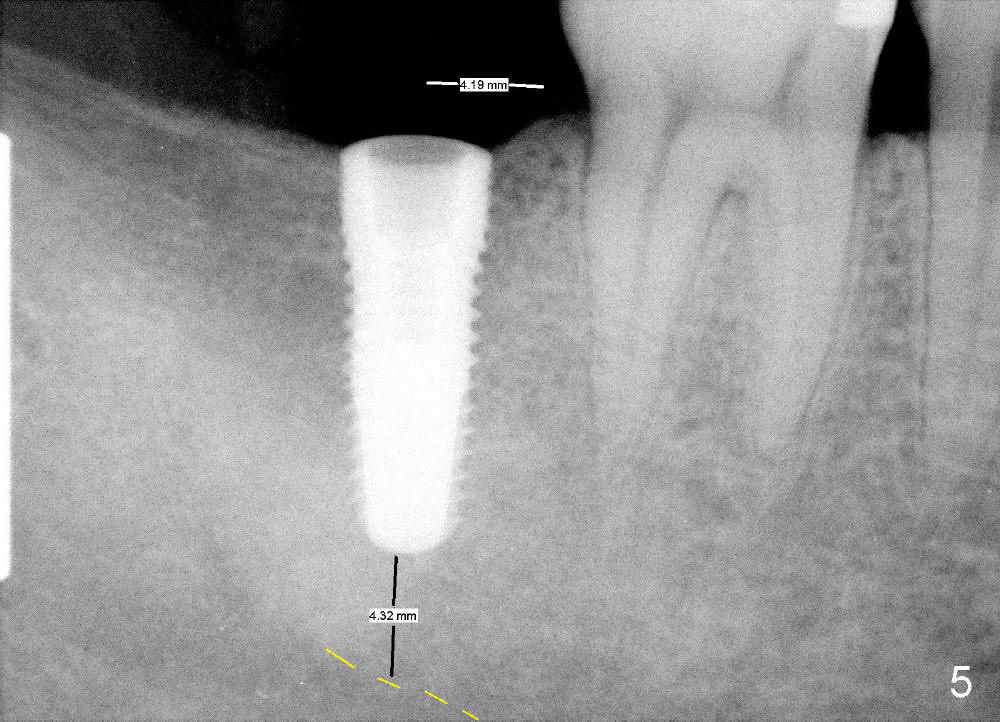

A 53-year-old man requests implant restoration for the lower right 2nd molar (Fig.1: LR2). A 5.3x14 mm submerged tapered implant is planned (Fig.2). PA is taken with a parallel pin after use of a 2 mm drill at the depth of 12 mm (Fig.3). It appears that the length of 14 mm has a safe margin (2-3 mm from the inferior alveolar nerve, yellow dashed line). In addition, the distance from the distal surface of the 1st molar is within normal limit (~5 mm).

With these two parameters under control, it is quick and safe to finish osteotomy with tapered drills with stoppers (Fig.4 <). Stoppers are particularly useful in the posterior region where visibility is limited. The implant is placed as planned (Fig.5, as compared to Fig.2).

The lower 2nd molar implant should be as short as possible and placed as low as possible particularly when the opposing tooth is supraerupted.